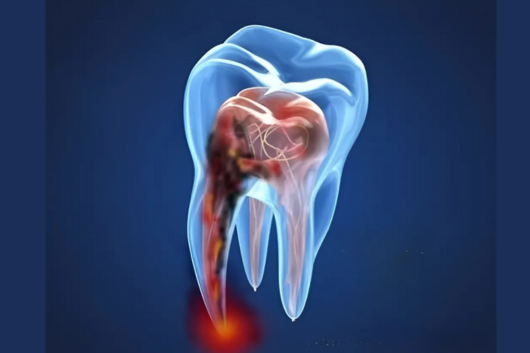

Single sitting Root canal Treatment

Tooth decay, when left untreated, can lead to pulp infection, causing pain and discomfort. The pulp — the soft tissue inside the tooth — contains blood vessels and nerves. Our single sitting root canal treatment removes the infected tissue and replaces it with a filling material to preserve the tooth. The best part? The entire procedure is pain-free and completed in just one session, relieving you from further complications.